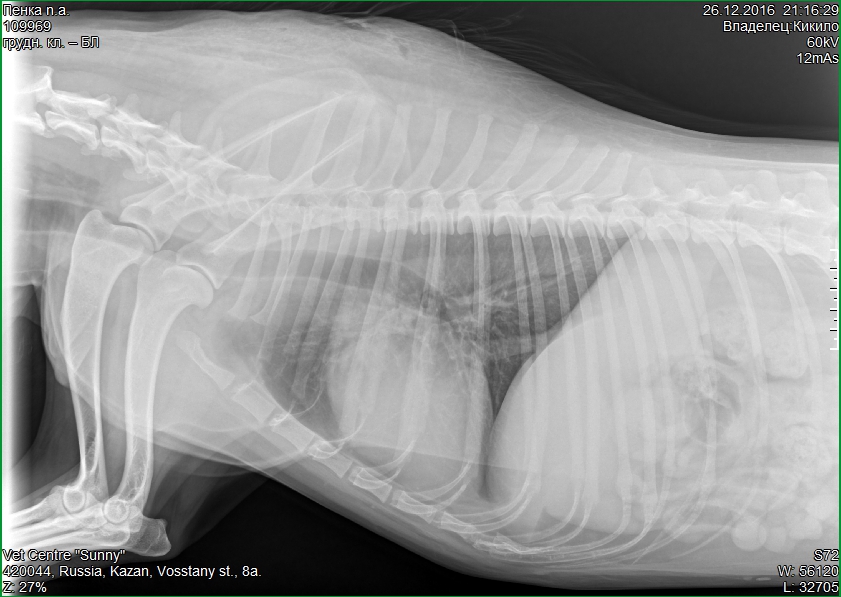

Мы поедем сегодня в другую клинику, где есть цифровой рентген - врачи сказали ехать туда((

час дороги, с собой лекарство возьмем... Надеюсь, что ничего страшного, у меня плохое ощущение

От рентгена будем плясать, антибиотики или что-то нам предложат. Я напишу здесь.

Мы рентген сделали, но пока без информации. Снимок отправили в Питер и нашему врачу, но она болеет, спит уже похоже( кстати, промыв нос больше не кашляет, купила ей смягчающую мазь в носик

Горбик на снимке наш абсцесс и похоже это зреет третий(( те два уже чистые, выделений крайне мало

По снимку врачи говорят, что видно низкое АД и низкий ОЦК и есть участок воспаления бронхов небольшой.

Не кушаем... Сегодня возьму перфузор, буду капать, увеличивать объем церкулирующей крови...